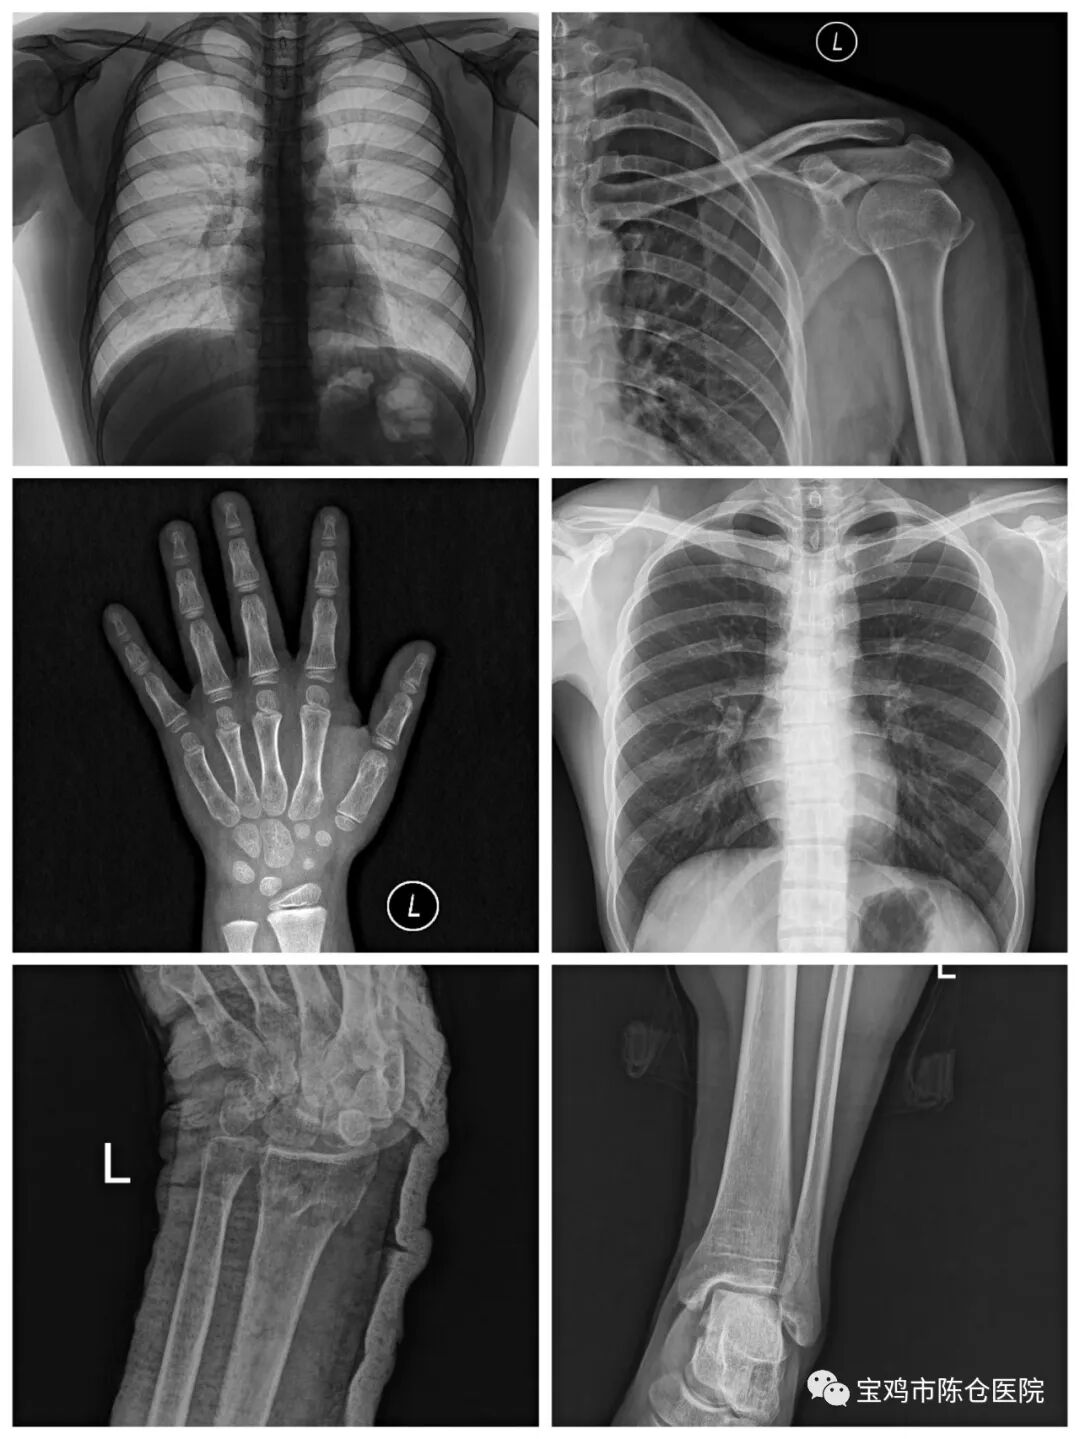

可开展的诊疗项目

常规透视、摄影检查

1.立位全胸部透视+摄影(无需切换)

2.卧位胸部、腹部摄影

3.四肢关节、脊柱摄影

4.头颅各体位摄影(包括各种角度的倾斜投照)

消化道透视摄影造影检查

1.食道造影

2.上消化道造影

3.全消化道造影

4.结肠气钡灌肠造影

特殊造影检查

1.吞咽造影

2.肝胆系统胆道碘剂造影:“T”管造影;经鼻胆管造影;经内镜逆行性胰胆管造影术(ERCP );PTC等。

3.静脉肾盂造影

4.子宫输卵管造影

5.膀胱造影

6.局部窦道造影

一机多用

该设备既可以完成消化道造影、静脉肾盂造影等各种造影检查,并可做头颅、脊柱、胸腹部及肩、髋、膝关节等全身各部位的数字化X线摄片,四肢全长及脊柱全长摄影;数字胃肠的检查床可以左右上下移动,可减少骨折等病人的移动。